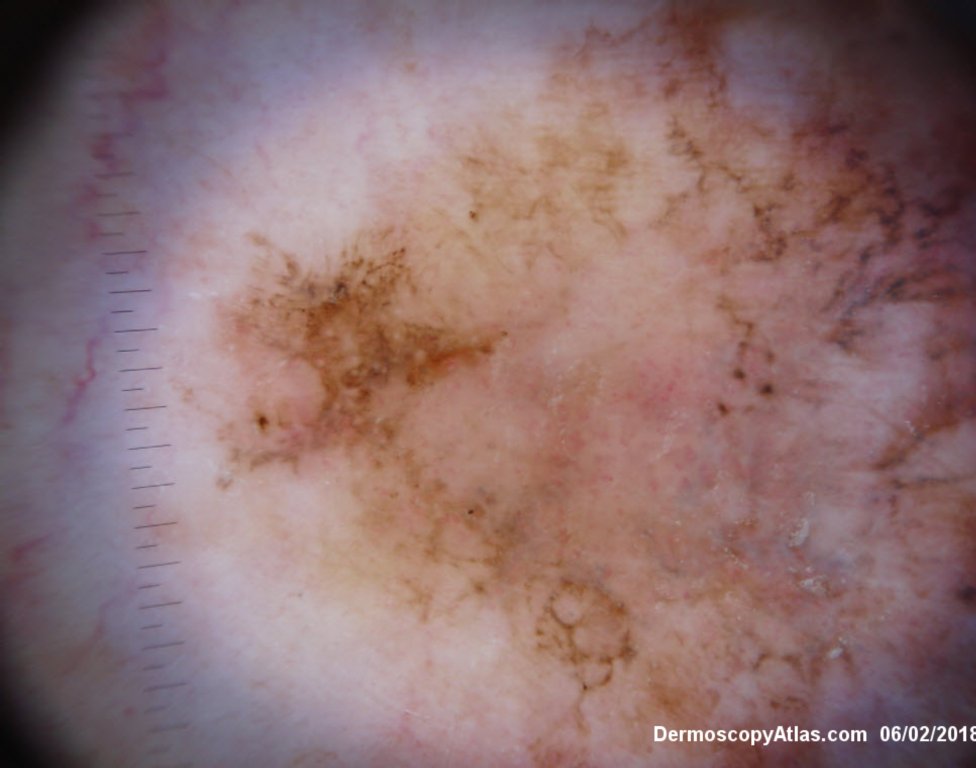

Description: Multiple colours in this pigmented lesion on the lower leg. New pink area

Lady in her early 80s who presented with this lesion on her ankle. The pigmented area had been there for some time but the pink area was bleeding and new. Shave of surrounding area and a punch biopsy of the new pink area showed mainly surrounding in situ melanoma with invasive melanoma in the pink area 1.8 mm thick. Having a 2cms margin excision of the whole area and a graft.